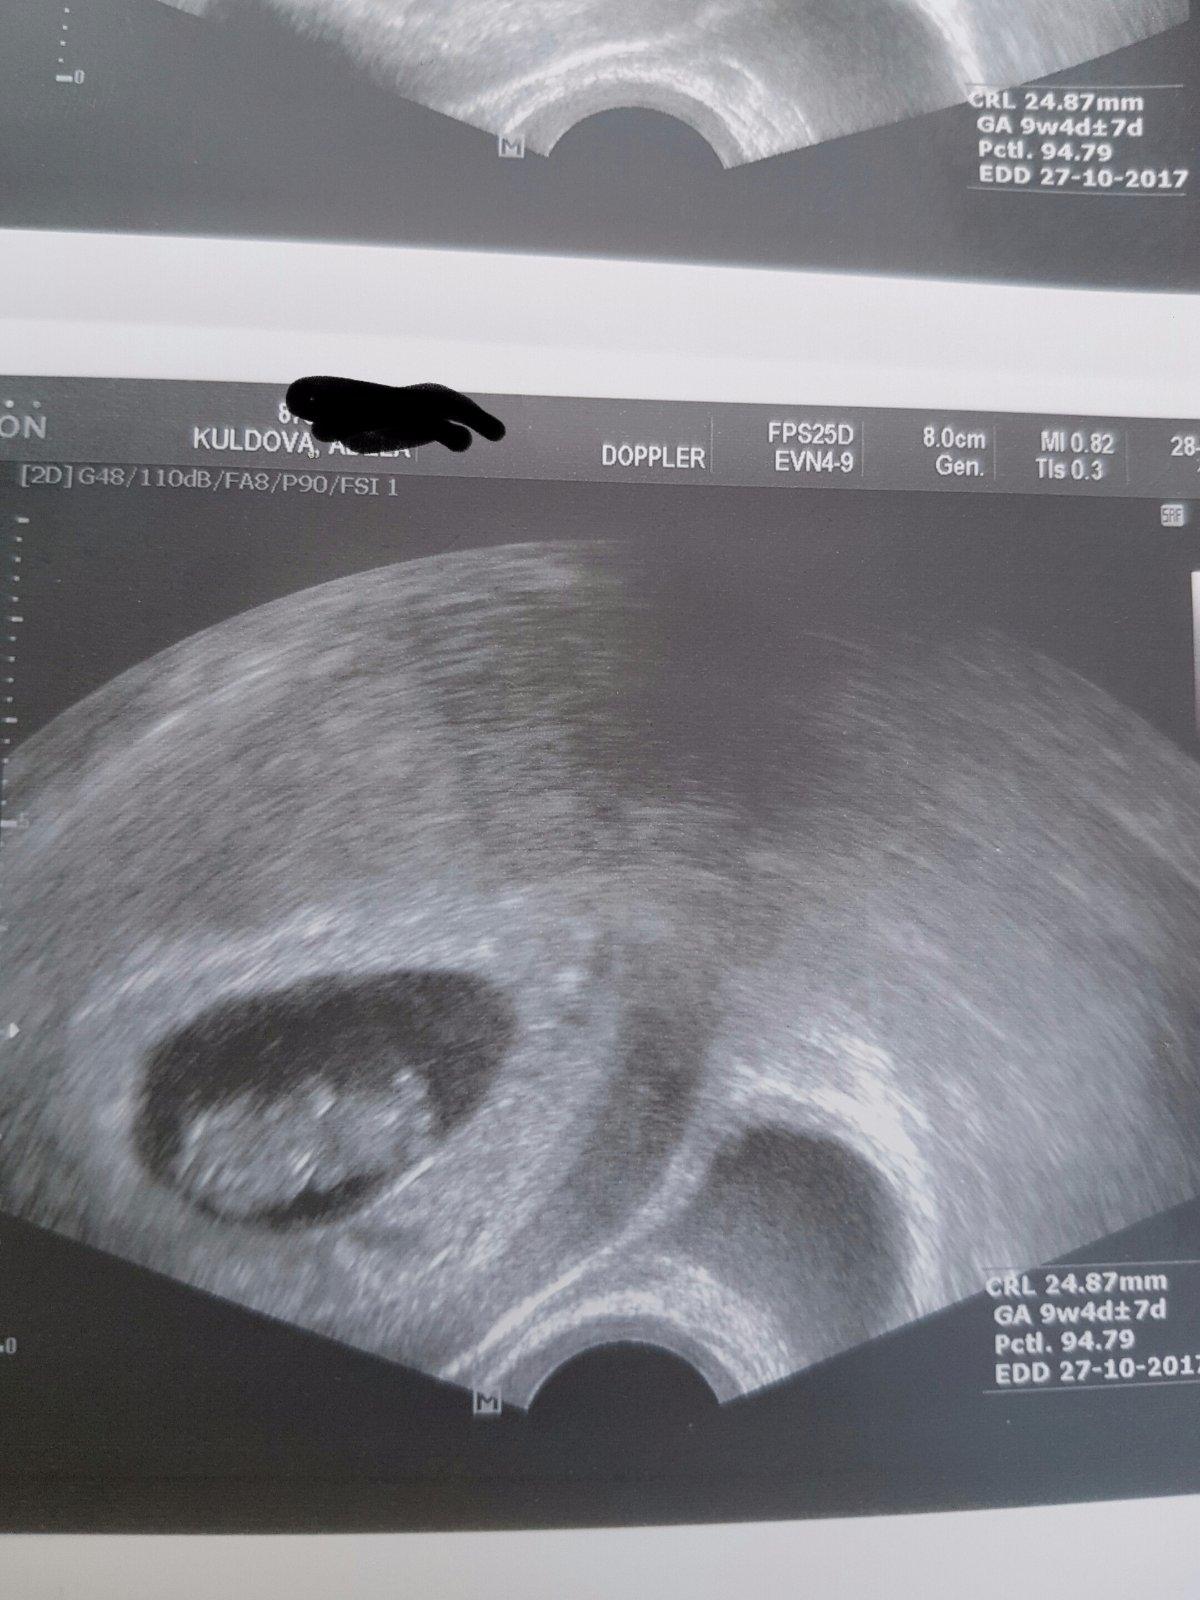

@adusku a ja az 25.4. dnes jsem 10+1 🙂

Holky!!! Dneska 7+1 a máme ❤👼🤰😃!!! Já mám takovou radost!!! Slyšeli jsme, jak ❤krásně bije a viděli, jak na ultrazvuku bliká!!! Přeji i vám, ať se tohoto okamžiku brzy dočkáte!!! Je to tak krásné!!! 😭😭😭❤